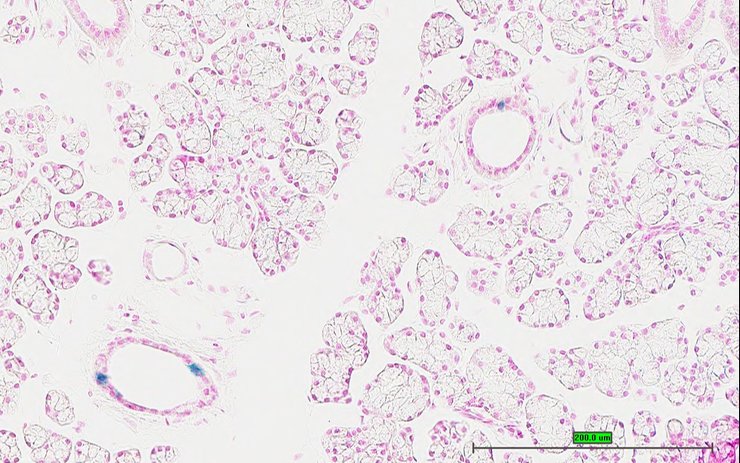

Specimen UC Davis_1878097: postnatal adult; Bacc1tm1.1(KOMP)Vlcg/Bacc1+ (more )

Structure Level Pattern Image Note

TS28: lung Present UC Davis_1878097

Specimen UC Davis_1878098: postnatal adult; Bacc1tm1.1(KOMP)Vlcg/Bacc1+ (more )

TS28: lung Present UC Davis_1878098

Specimen UC Davis_1878099: postnatal adult; Bacc1tm1.1(KOMP)Vlcg/Bacc1+ (more )

TS28: lung Present UC Davis_1878099

Specimen UC Davis_1878100: postnatal adult; Bacc1tm1.1(KOMP)Vlcg/Bacc1+ (more )